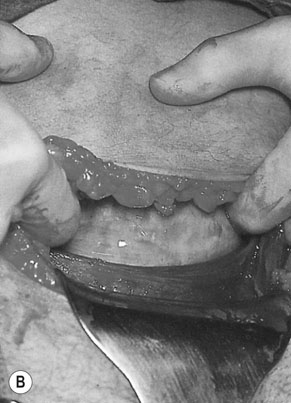

Examples of the types of forceps used when no anterior rotation of the head is required are the Neville Barnes and Simpson’s forceps (Fig. 12.8). Both of these forceps have cephalic and pelvic curves. The two blades of the forceps are designated according to the side of the pelvis to which they are applied. Thus the left blade is applied to the left side of the pelvis (Fig. 12.10A). There is a fixed lock between the blades (Fig. 12.10B). The two sides of the forceps should lock at the shank without difficulty. The sagittal suture should be perpendicular to the shank, the occiput 3–4 cm above the shank and only one finger space between the heel of the blade and the head on either side. Intermittent traction is applied coinciding with the uterine contractions and maternal bearing down efforts in the direction of the pelvic canal (Fig. 12.10C) until the occiput is on view and then the head is delivered by anterior extension (Fig. 12.10D).